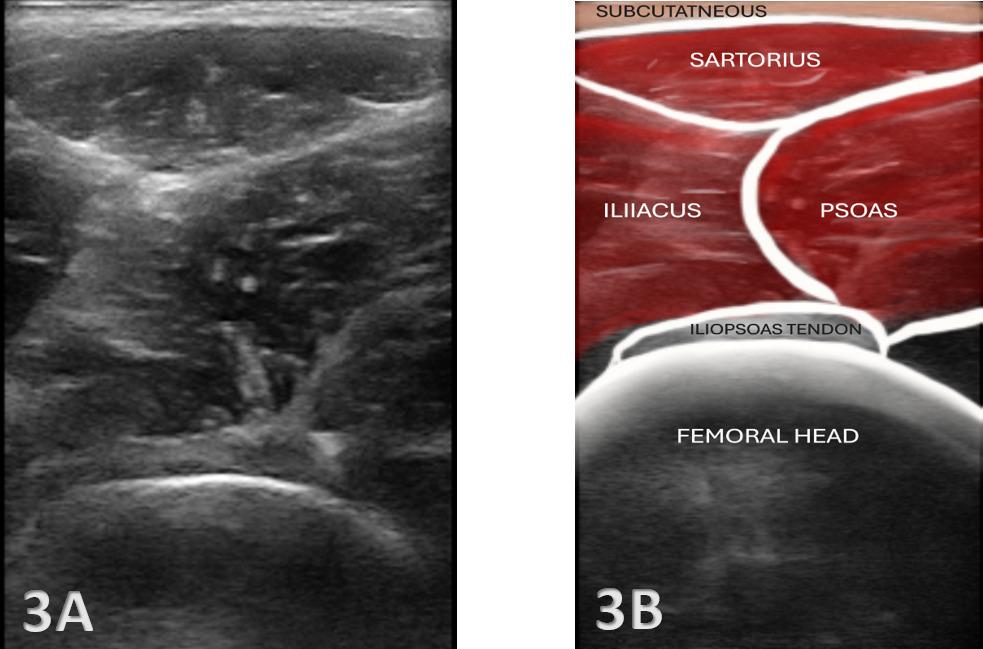

26. Ekstrand J, Lundqvist D, Davison M, D’Hooghe M, Pensgaard AM. Communication quality between the medical team and the head coach/manager is associated with injury burden and player availability in elite football clubs. Br J Sports Med 2019;53(5):304-308. doi:10.1136/ bjsports-2018-099411

27. Little C, Lavender AP, Starcevich C, et al. Understanding fear after an anterior cruciate ligament injury: a qualitative thematic analysis using the common-sense model. Int J Environ Res Public Health 2023;20(4). doi:10.3390/ijerph20042920

Solie B, Carlson M,

C,

Oh, My Quad: A Clinical Commentary And Evidence-Based Framework for the Rehabilitation of Quadriceps Size and Strength after Anterior Cruciate Ligament Reconstruction. IJSPT. 2024;19(12):1600-1628. doi:10.26603/001c.126191

Braidy

Solie1 a , Mitchell Carlson2 , Christopher Doney1 , Michael

Kiely

3 , Robert LaPrade4

1 Physical Therapy, Twin Cities Orthopedics, 2 Bioengineering Lab, Twin Cities Orthopedics , 3 Sports Science, Twin Cities Orthopedics, 4 Orthopedic Surgery, Twin Cities Orthopedics